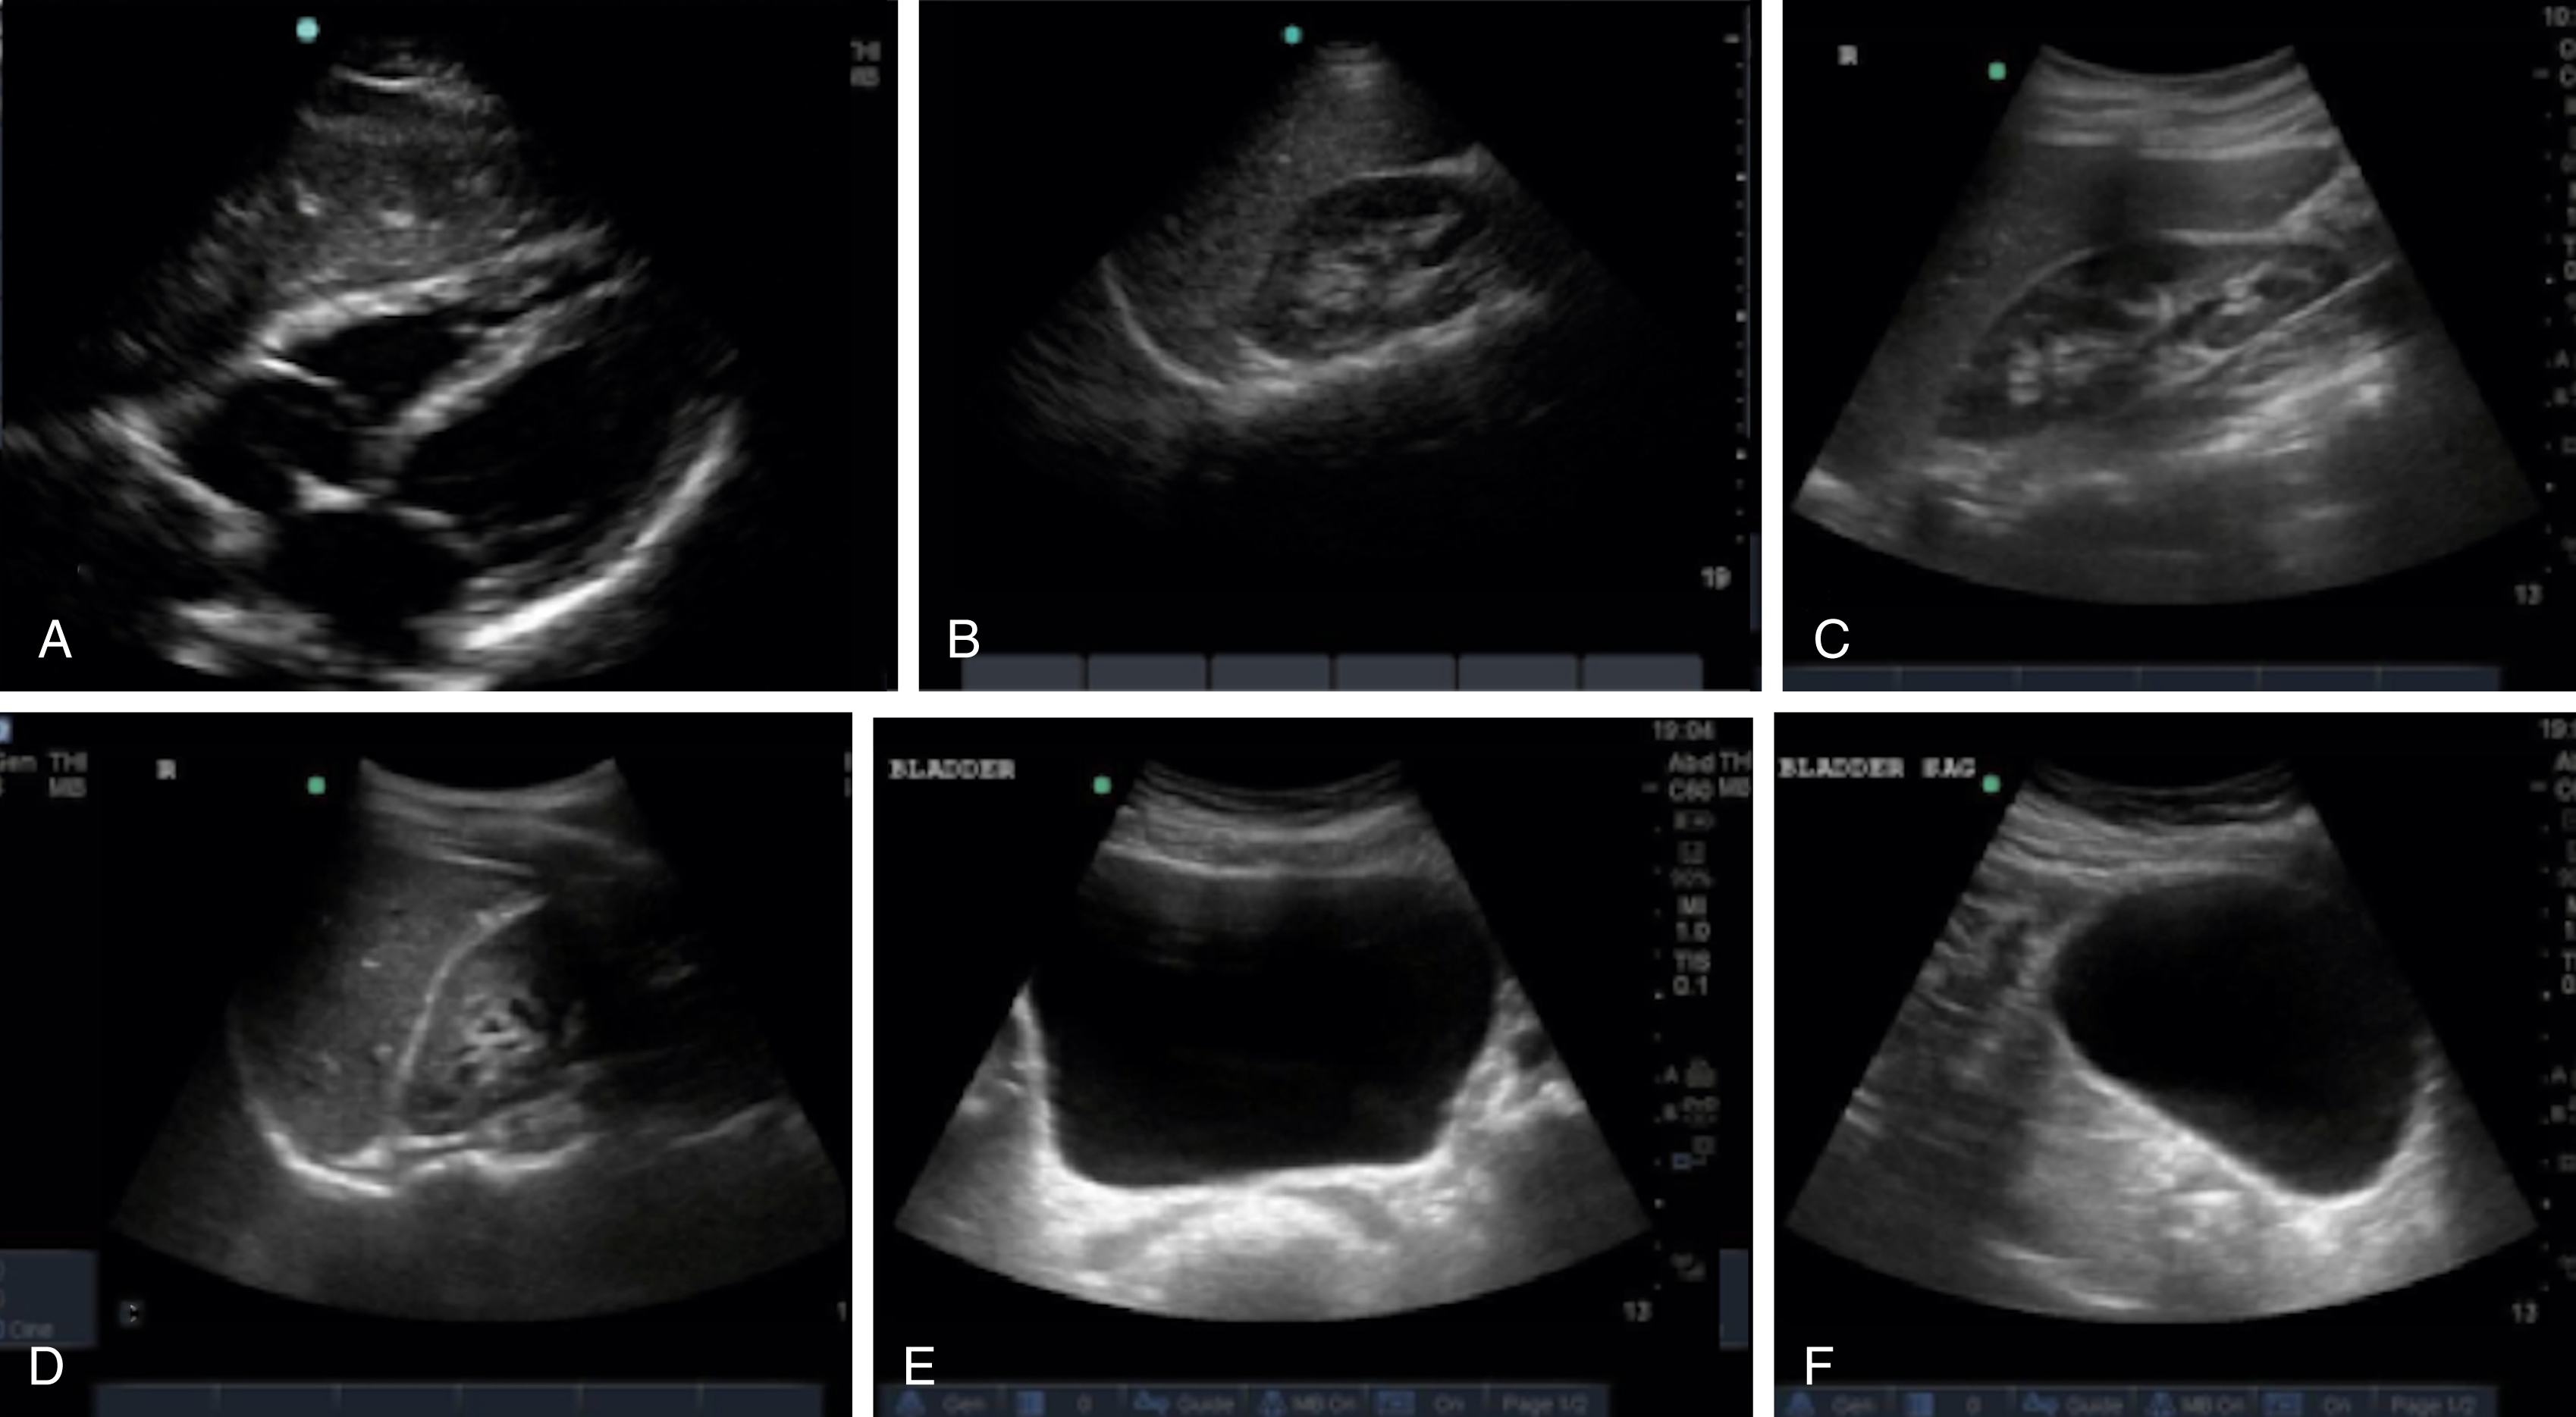

The FAST examination technique uses a low-frequency broadband transducer (2–6 MHz) to evaluate dependent peritoneal spaces, pleural spaces, and the pericardium for free fluid, which in the trauma patient is presumed to be blood. There are four main components of the basic FAST examination: (1) the right upper quadrant (RUQ) view, (2) the left upper quadrant (LUQ) view, (3) the pelvic view and (4) the cardiac view ( Fig. e3.1 ). The E-FAST includes anterior chest views to evaluate for pneumothorax. The RUQ view evaluates for fluid in the thorax (above the diaphragm) ( Video e3.1 ), hepatorenal space (Morison pouch) and the paracolic gutter (inferior edge of the liver and right kidney) ( Video e3.2 ), moving cephalad to caudad. The LUQ view, found slightly more superior and posterior than the RUQ, should mimic the RUQ views, but also include the subdiaphragmatic space, because free intraperitoneal fluid tends to accumulate here initially. The pelvis should be evaluated in the transverse and longitudinal planes, where fluid may be detected deep to the uterus (in females) or in the retrovesical space (in males) ( Video e3.3 ). The cardiac evaluation can be performed in either the subcostal (or subxiphoid) or parasternal window ( Video e3.4 ). Evaluation for pneumothorax uses a low or high-frequency transducer at a shallow depth, placed along the anterior chest wall and will be discussed in more detail in subsequent sections.

Negative FAST images. (A) Subxiphoid view with no pericardial effusion. (B) Negative RUQ view showing the thorax and hepatorenal space without the paracolic gutter visualized. There is mirroring and loss of the spine, indicating a negative thorax. (C) Negative paracolic gutter area by the liver tip in the RUQ view. (D) LUQ view showing negative thorax, as in B, and splenorenal space. (E) Negative transverse bladder view. (F) Negative sagittal bladder view.